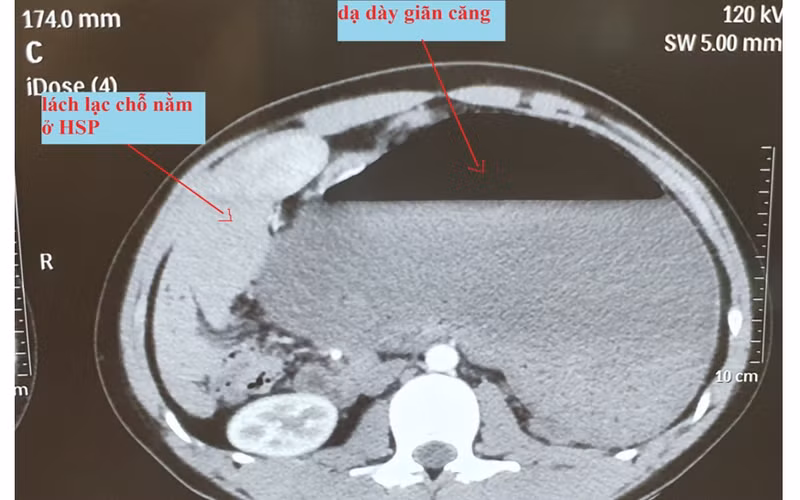

Hình ảnh chụp cắt lớp vi tính của bệnh nhân. Ảnh: BV.

Hình ảnh cắt lớp vi tính cho thấy dạ dày giãn căng, lách lạc chỗ nằm vị trí hạ sườn phải ngay dưới gan, thận trái lạc chỗ nằm ở hố lách.

Tổn thương trong mổ thấy dạ dày tự xoắn theo trục mạc treo của nó, 180 độ, cùng chiều kim đồng hồ, giãn căng, kéo theo lách sang vị trí hạ sườn phải. Trên nền bệnh nhân có bất thường giải phẫu cơ hoành: vùng cơ hoành trái phía trên hố lách dị dạng tạo thành một hốc lớn ở phía sau, thận trái lạc chỗ nằm ở hốc này. Dạ dày xoắn chưa có biểu hiện hoại tử.